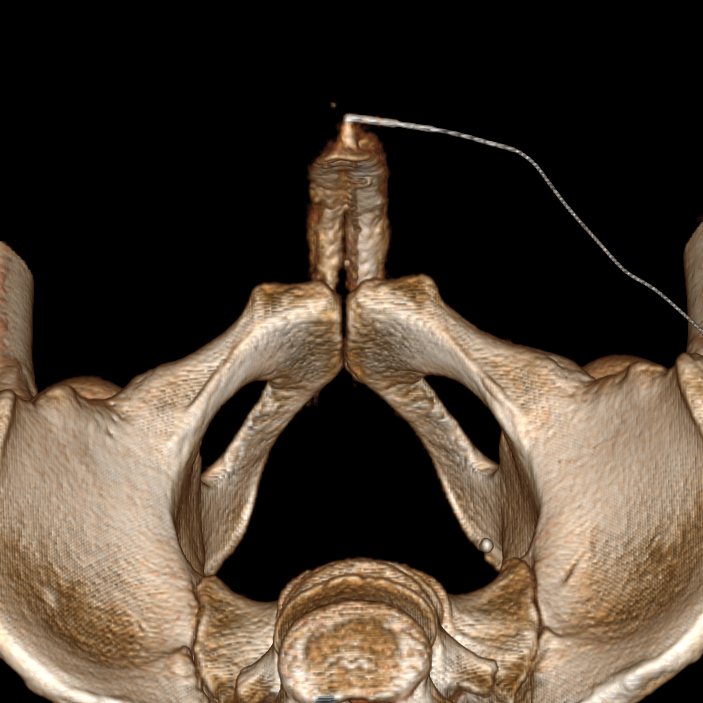

3. При венозной утечке уролог может отправить вас на абсолютно демоническую методику (которой в целом я и занималась) — КТ-кавернозографию. Однако, именно этот метод демонстрирует нам куда что утекает, и с какими сосудами будет работать сосудистый хирург. Хирург эмболизирует те сосуды, в которые происходит венозная утечка, таким образом на длительной время (пока не развились новые венозные коллатерали) обеспечит поддержание эрекции.